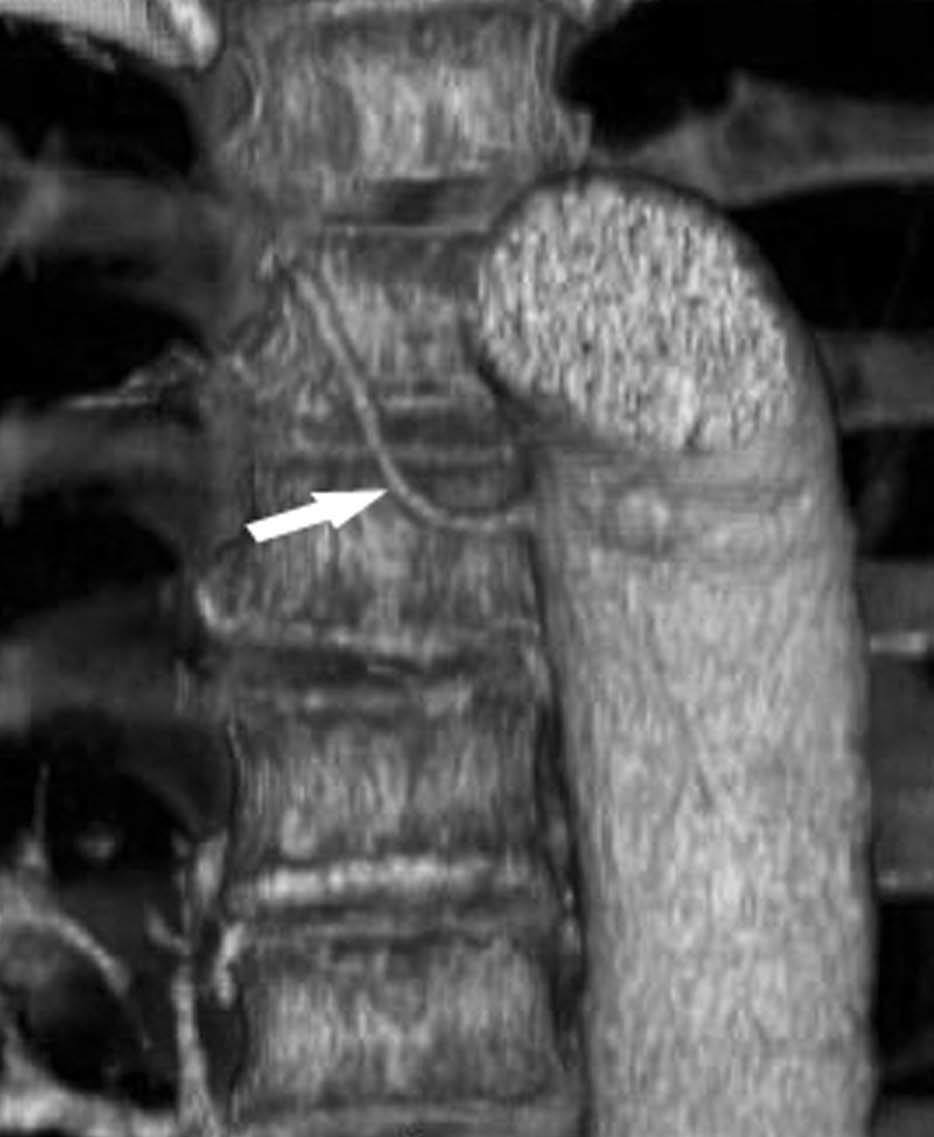

La resonancia magnética (RM) se utiliza principalmente para solventar problemas puntuales, y cada vez se emplea menos dado que la TCMD se ha equiparado con la RM en la capacidad de reconstruir en cualquier plano del espacio. Actualmente, la RM se debe reservar para la evaluación de los tumores del sulcus superior, aunque hay autores que consideran que debe emplearse sólo cuando existe invasión del canal medular, ya que en el resto de las situaciones la TCMD da suficiente información para obviar dicha técnica10 (fig. 10).